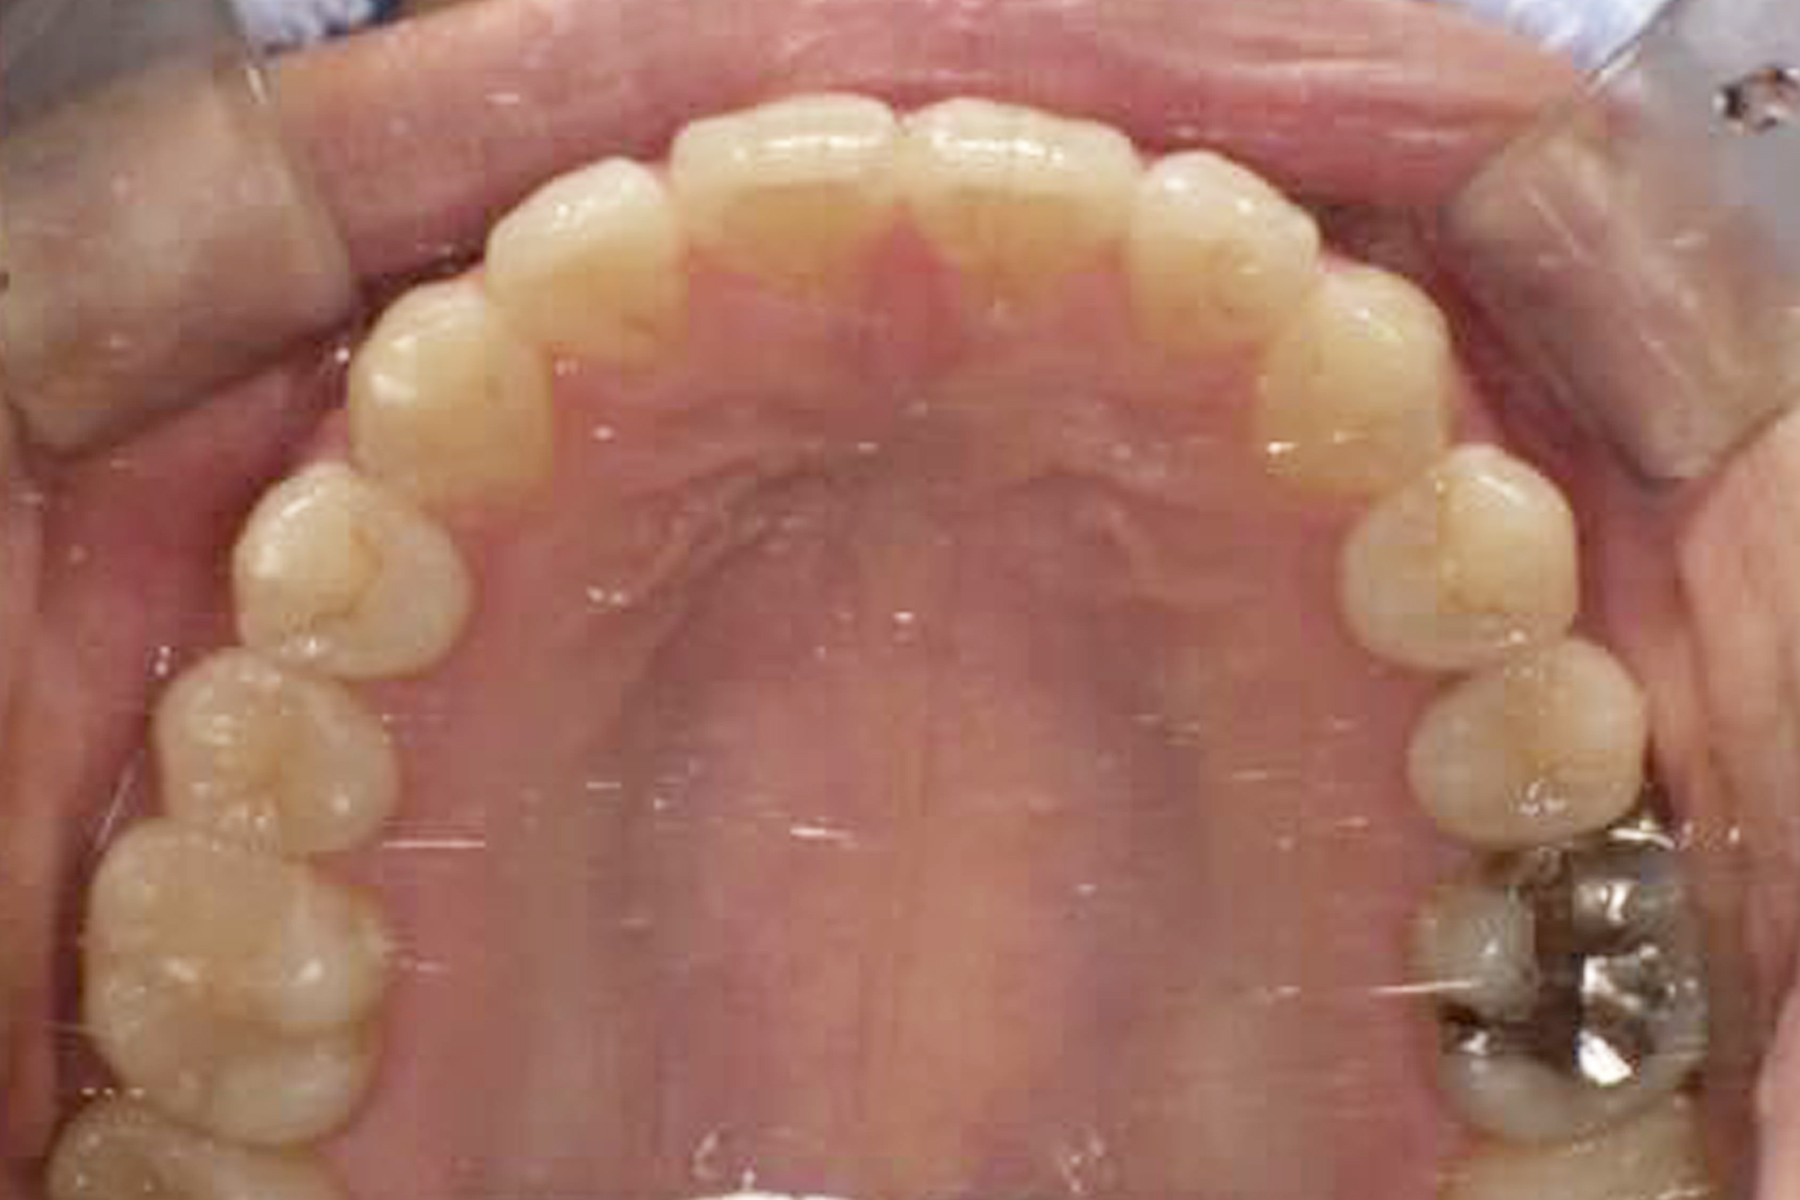

Case.1

BEFORE

AFTER

| 担当医 | 林 大貴 |

|---|---|

| 主訴 | 歯並びを直したい |

| 期間 | 約6ヶ月 |

| 費用 | 550,000円 |

| 治療内容 | マウスピース矯正 |

| 治療に伴うリスク | 動的治療後、保定装置を決められた期間確実に装着しなかったり した場合後戻りが起こる可能性があります。 |